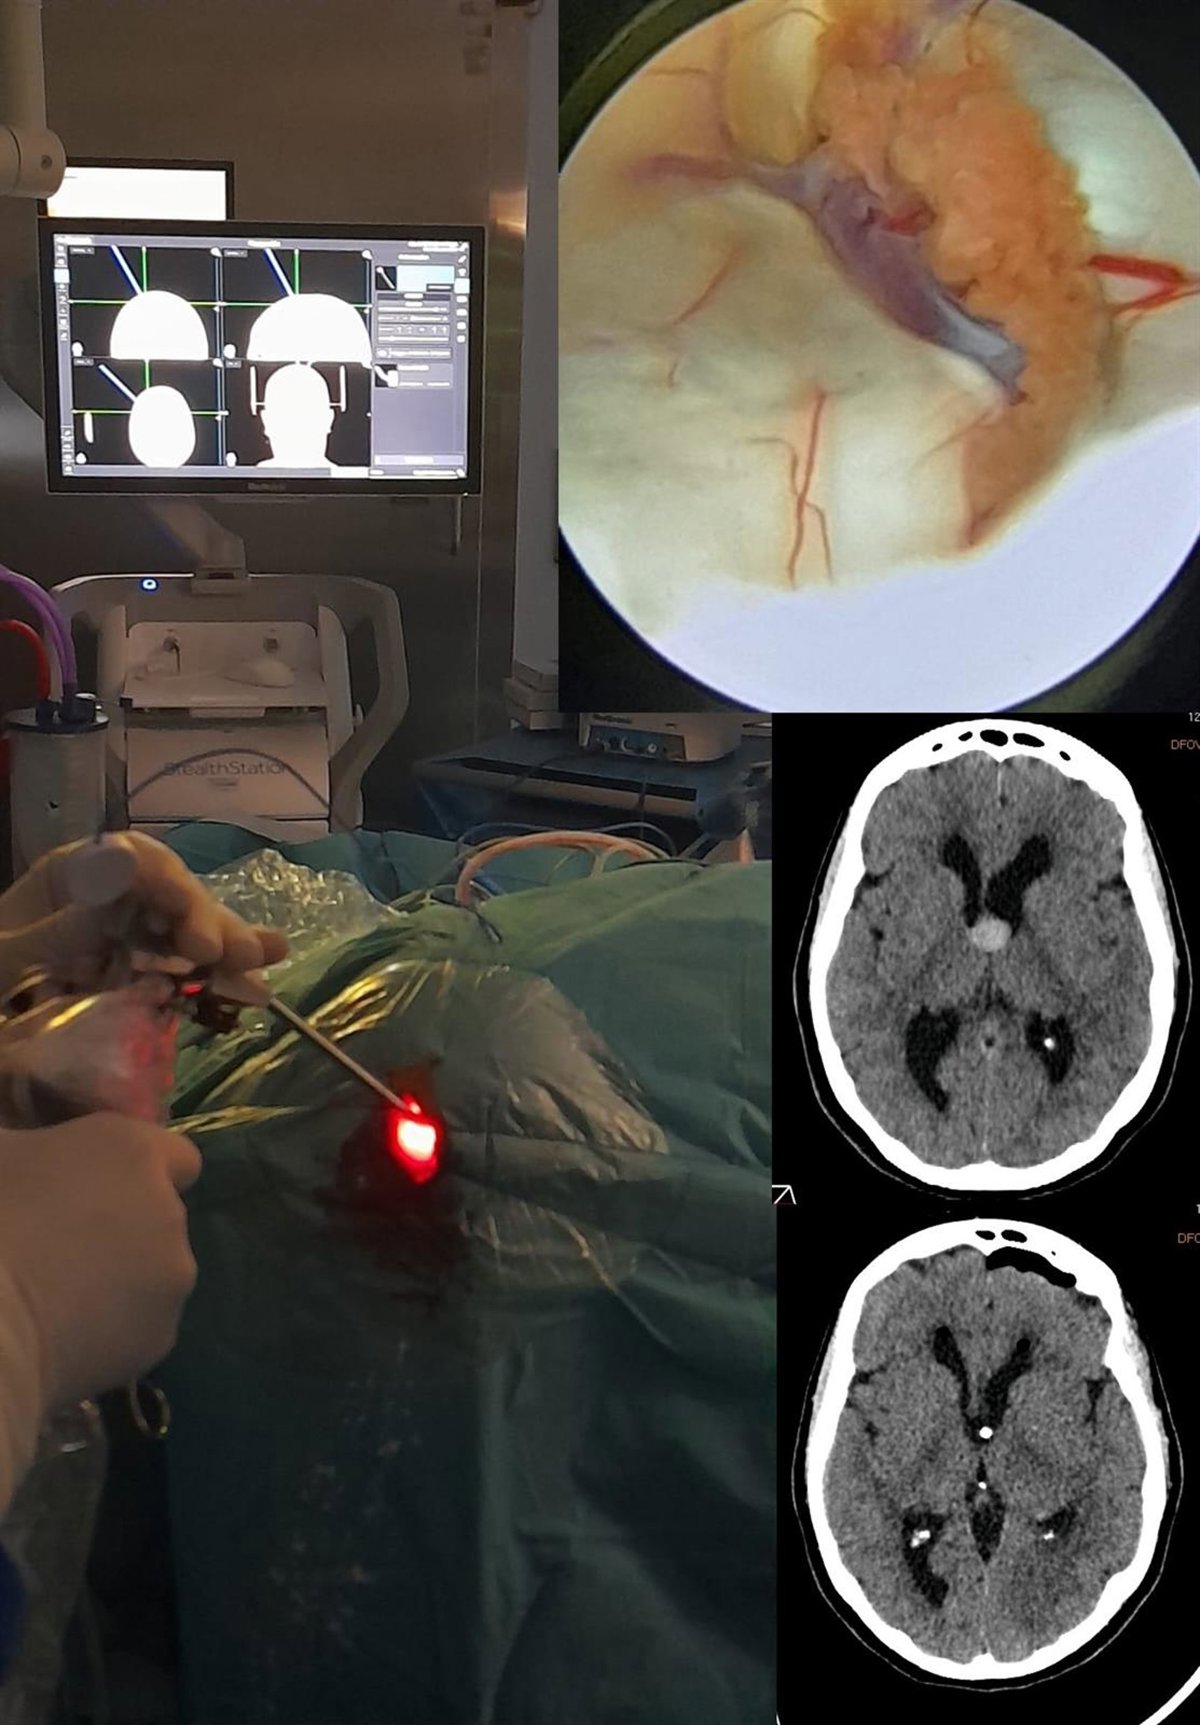

El Hospital Vithas Granada ha realizado recientemente con éxito una cirugía endoscópica cerebral que ha consistido en la extirpación de un quiste coloide intraventricular mediante un procedimiento endoscópico, técnica considerada muy compleja, pero poco invasiva.

La intervención ha sido llevada a cabo por el equipo de neurocirugía del Hospital Vithas Granada, según detalla el centro hospitalario desde una nota en la que precisa que los quistes coloides son lesiones benignas cuyo crecimiento provoca obstrucción en la circulación del líquido cefalorraquídeo (hidrocefalia).

Para ello, la endoscopia intraventricular permite la extirpación de estas lesiones a través de un orificio de tan solo tres centímetros por el que se introduce un endoscopio, a través del cual se realiza la cirugía. El procedimiento se lleva a cabo asistido con navegación cerebral, con el que se planifica el trayecto del endoscopio para minimizar las complicaciones.

Se trata de un procedimiento mínimamente invasivo, pero técnicamente complejo, no al alcance de todos los neurocirujanos. Y, en este caso, el equipo de Neurosalus21 del Hospital Vithas Granada cuenta entre sus especialistas con la doctora Ana María Román, reconocida experta en este tipo de intervenciones, por lo que la cirugía se llevó a cabo con total éxito hasta tal punto que la paciente recibió el alta tan solo 48 horas después de la operación.